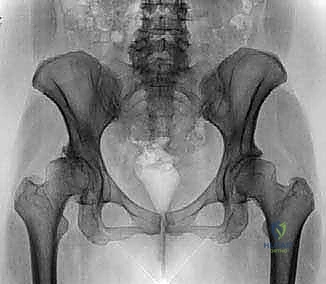

1. الاصطدام الفخذي الحقي (Femoroacetabular Impingement - FAI)

وهي حالة شائعة جداً تحدث عندما تنمو نتوءات عظمية زائدة إما على رأس عظمة الفخذ (Cam) أو على حافة تجويف الحوض (Pincer)، أو كليهما. هذا النمو الزائد يؤدي إلى احتكاك غير طبيعي أثناء الحركة، مما يمزق الشفا الغضروفي ويتلف الغضروف المفصلي.

- الأشعة السينية (X-rays): لتقييم العظام، والتأكد من وجود نتوءات عظمية (FAI) أو علامات مبكرة لخشونة المفصل.